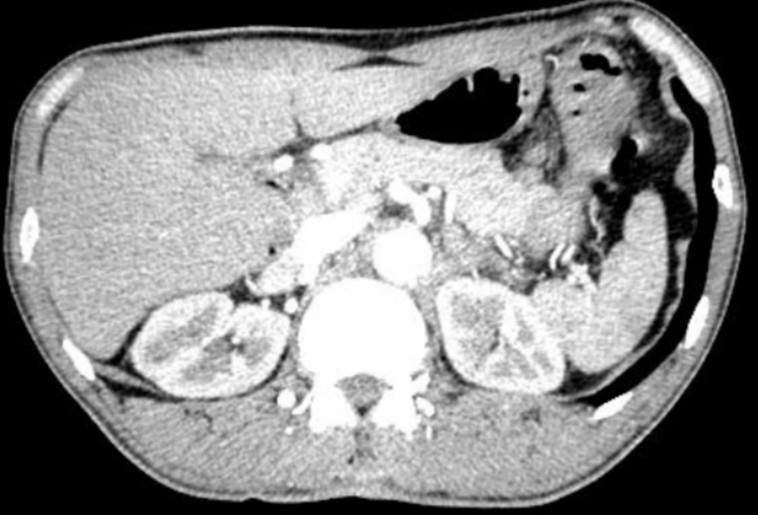

- Chụp cắt lớp vi tính ổ bụng:

Hình 2. Hình ảnh chụp CTscanner ổ bụng hiện tại không thấy bất thường.